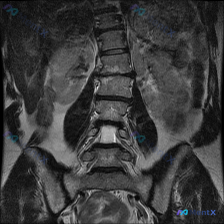

整理到一张腰椎MRI的冠状位T1WI图像,先不说结论,大家第一眼会怎么看? 目前能看到的影像表现: - 腰椎明显向右侧凸,有椎体旋转和倾斜 - 两侧椎间隙高度不均匀,部分变窄 - 多个椎间盘信号降低 - 椎体骨髓信号基本是弥漫中等偏高,没看到明确的局灶骨质破坏或大肿块 - 两侧腰大肌形态不对称 这份...